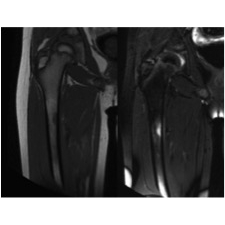

| Thigh Pain In A Collegiate Cross-country Runner - Page #3 | |||